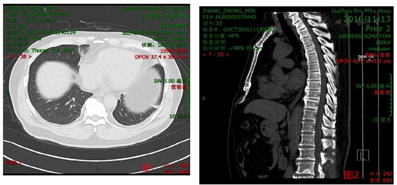

2017年2月14日我院门诊入院前检查:⑴胸部CT:左肺上叶下舌段及左肺下叶少许炎性病变,左侧胸膜及右下肺胸膜炎症、并左侧胸腔少量积液,见图1;⑵胸椎MR平扫:胸椎退行性变:胸椎体骨质增生,胸椎间旁变性,左下肺肺炎症,左侧胸腔少量积液,腰椎退行性变:腰3-4间盘终板炎,腰3椎体上、下缘许莫氏结节,腰2-5椎间盘膨出,腰椎骨质增生,见图2。